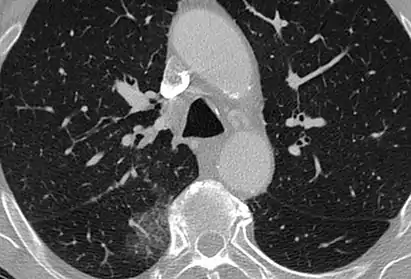

CT image showing mosaic attenuation pattern in patient with hypersensitivity pneumonitis. Note the alternating, patchy areas of increased and decreased attenuation, particularly in the left lung (screen right).

Mosaic

A mosaic pattern of GGO refers to multiple irregular areas of both increased attenuation and decreased attenuation on CT. It is often the result of occlusion of small pulmonary arteries or obstruction of small airways leading to air trapping.[6] Sarcoidosis is an additional cause of a mosaic GGOs due to the formation of granulomas in interstitial areas. This may coexist with granulomatosis with polyangiitis, leading to diffuse areas of increased attenuation with ground-glass appearance.[6]